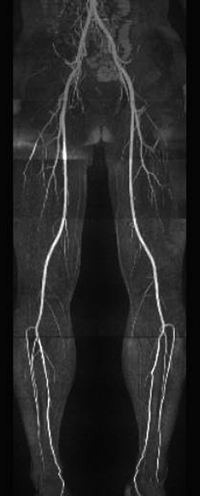

自由呼吸下で動きによるアーチファクトを除去し撮像を行います(StarVIBE)